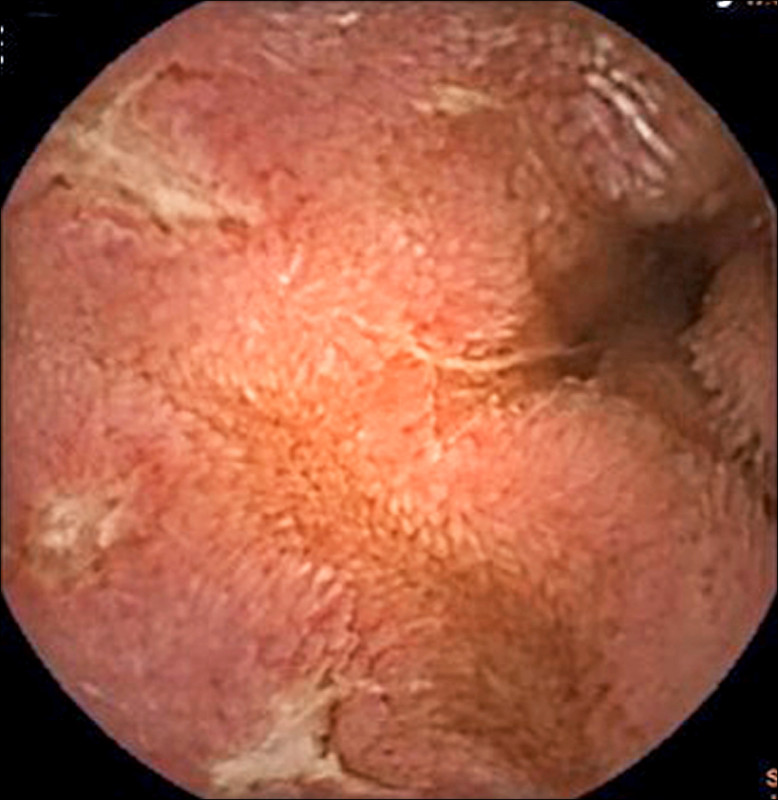

章振旺說,這名男性業務員經膠囊內視鏡檢查,結果顯示,小腸從空腸到迴腸多處可見跳躍式病灶及縱向潰瘍,經影像與病理檢查綜合判讀,確認為克隆氏症,在接受類固醇與免疫調節藥物治療後,病情已大幅穩定,體重也不再下降。

章振旺指出,小腸疾病較難以利用傳統腸鏡檢查一窺全貌,膠囊內視鏡正好補足盲點,對克隆氏症早期發現與評估病灶嚴重程度有極大幫助。